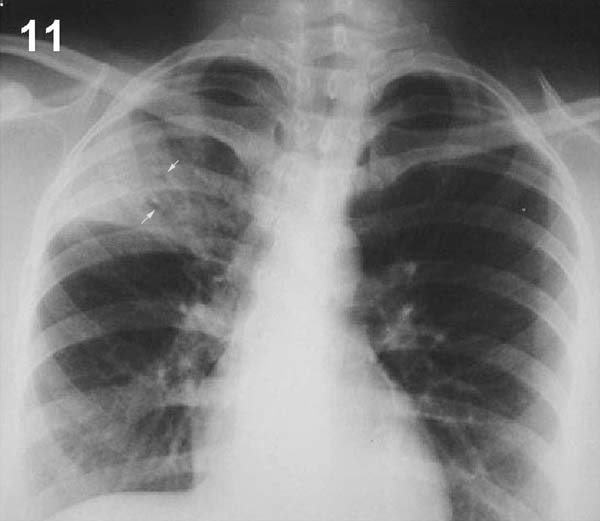

PLACA 11